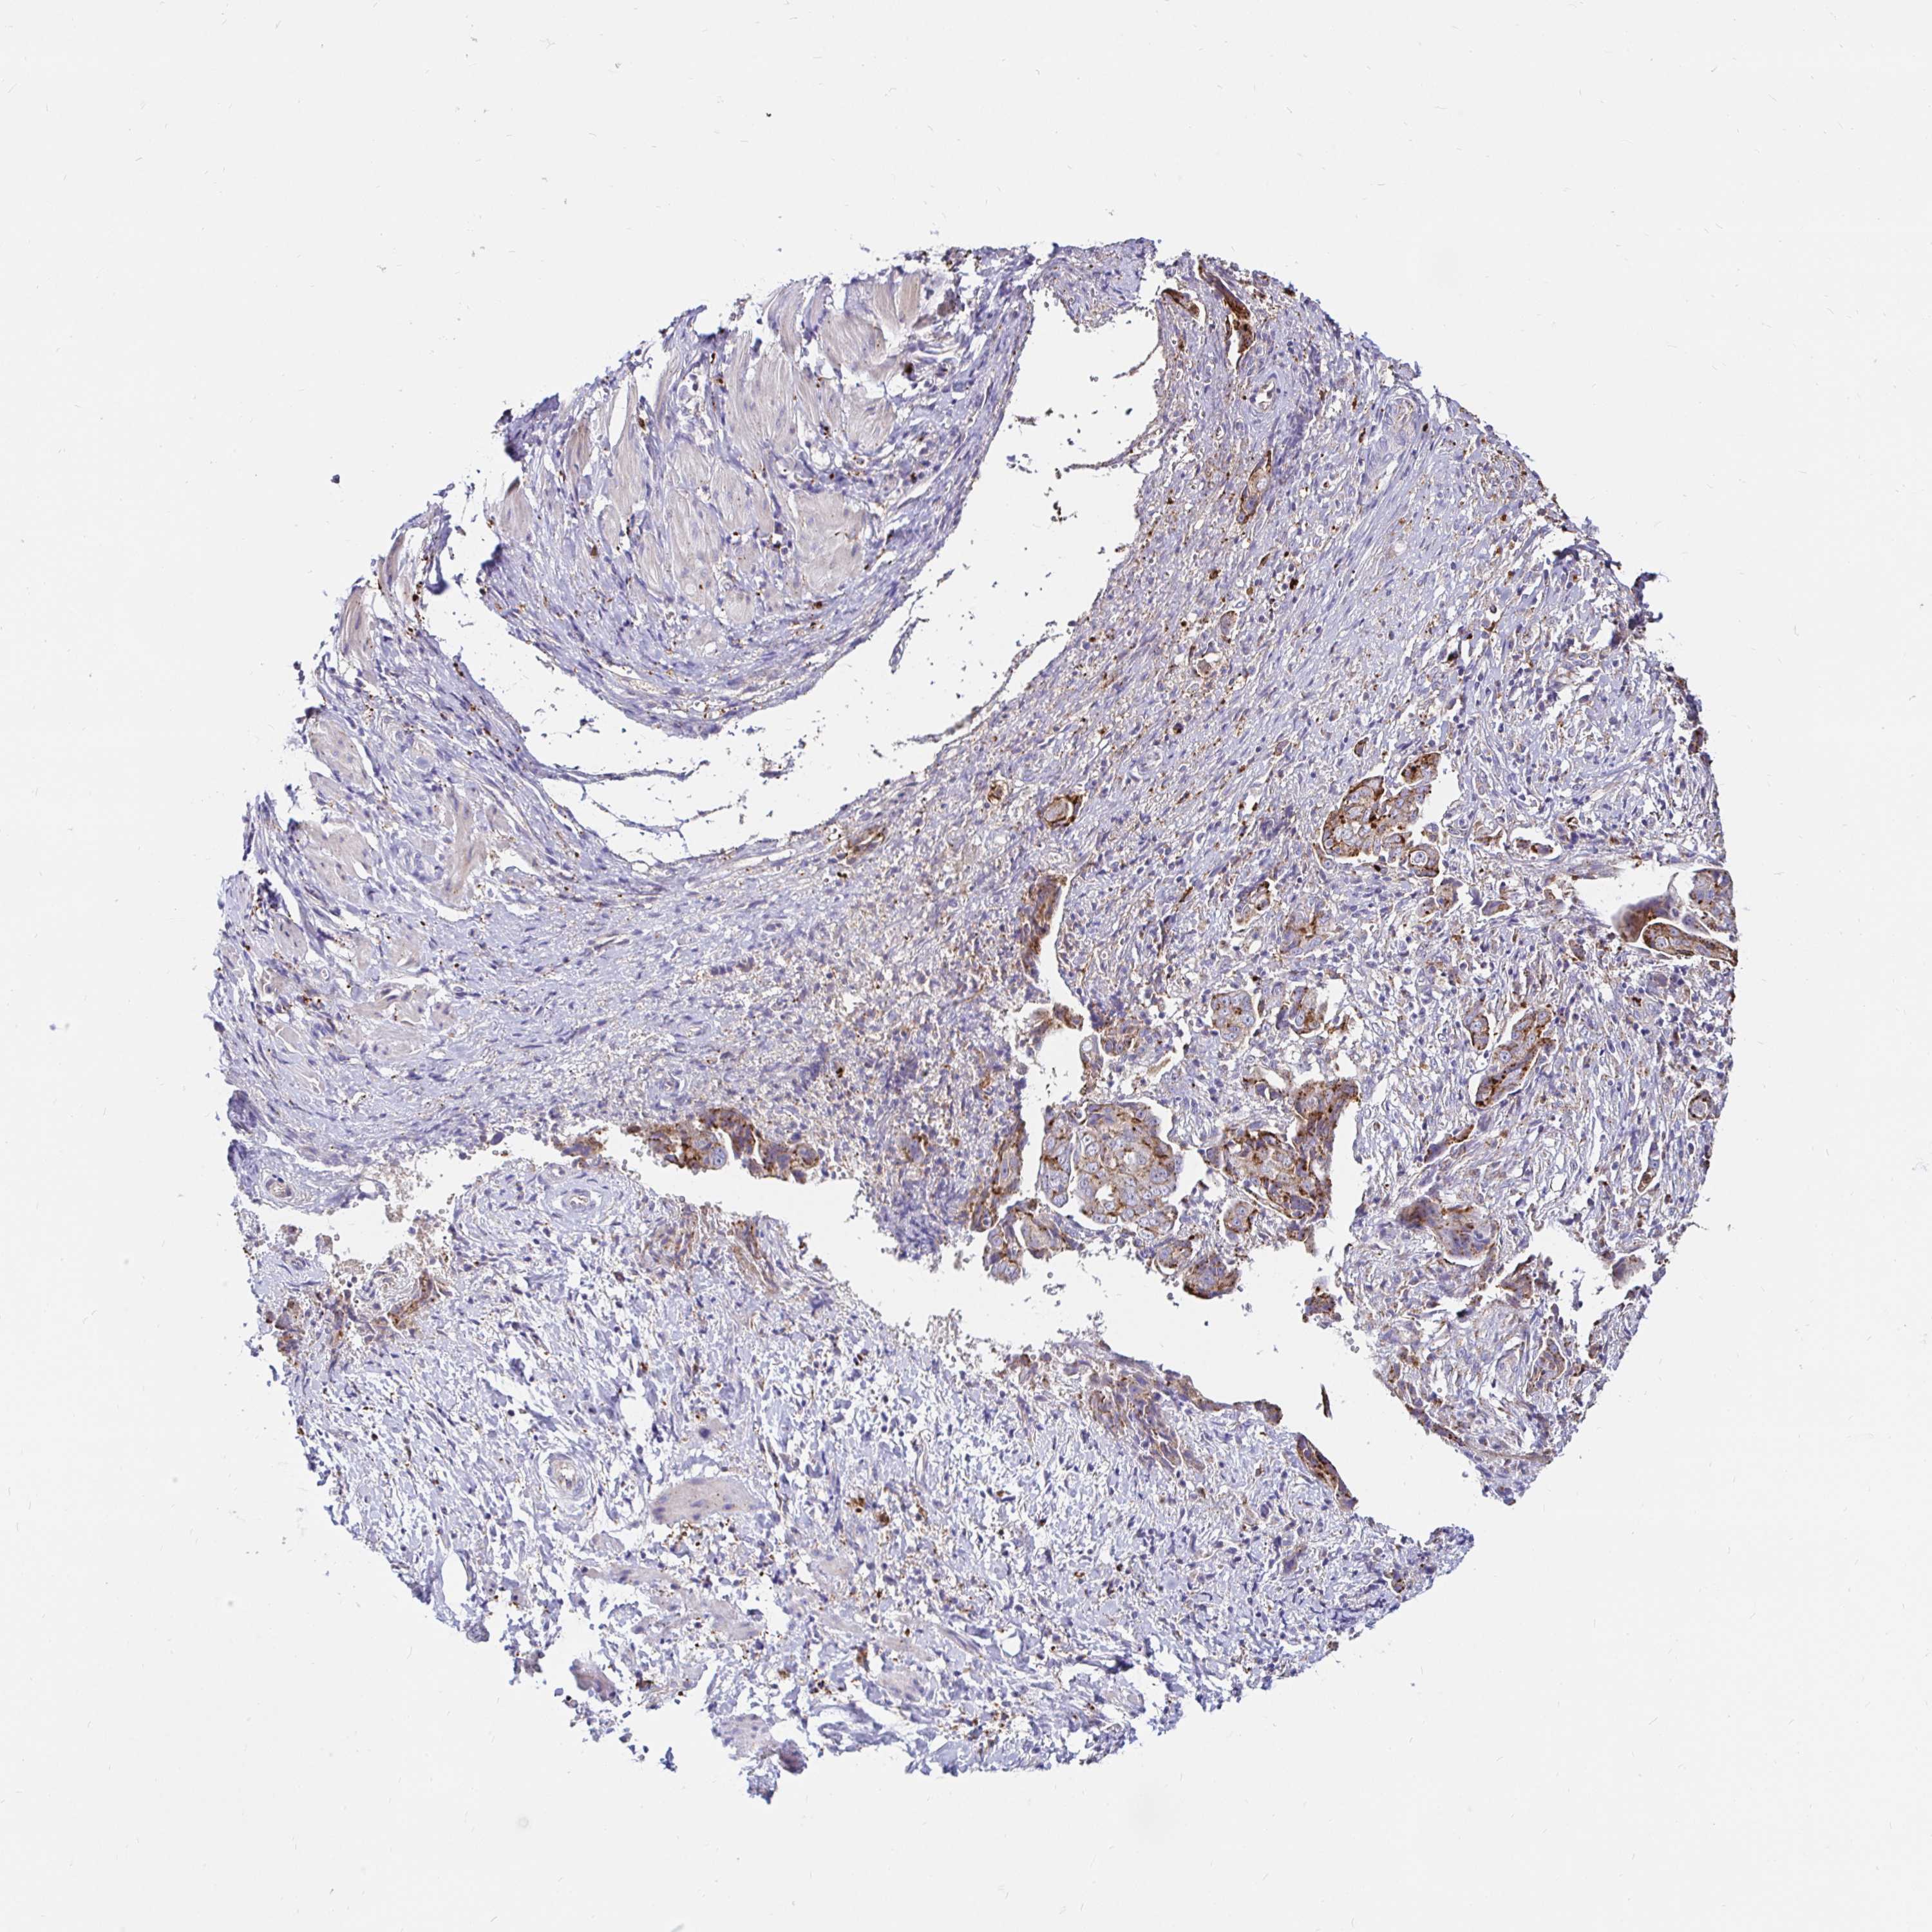

OVARIAN CANCER - Protein expressioni

A mouse-over function shows sample information and annotation data. Click on an image to view it in a full screen mode. Samples can be filtered based on level of antibody staining by selecting one or several of the following categories: high, medium, low and not detected. The assay and annotation is described here.

Note that samples used for immunohistochemistry by the Human Protein Atlas do not correspond to samples in the TCGA dataset.

Antibody stainingi

Antibody staining in the annotated cell types in the current human tissue is reported as not detected, low, medium, or high, based on conventional immunohistochemistry profiling in selected tissues. This score is based on the combination of the staining intensity and fraction of stained cells.

Each image is clickable and will lead to virtual microscopy that enables deeper exploration of all samples and also displays staining intensity scores, fraction scores and subcellular localization as well as patient and tissue information for each sample.

Antibody HPA046542

Antibody HPA056371

Staining

High

Medium

Low

Not detected

Intensity

Strong

Moderate

Weak

Negative

Quantity

>75%

75%-25%

<25%

None

Location

Nuclear

Cytoplasmic/membranous

Cytoplasmic/membranous,nuclear

Cystadenocarcinoma, serous, NOS

Carcinoma, NOS

Cystadenocarcinoma, mucinous, NOS

Carcinoma, endometroid